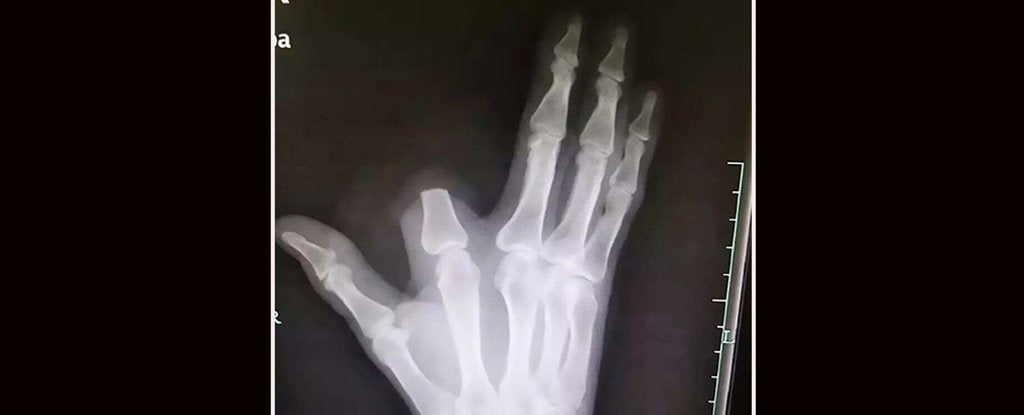

Y sí, cortar de raíz es eso que estás pensando. Al parecer, la historia tuvo lugar en China, donde un hombre estaba cortando leña cerca de su pueblo en las montañas del distrito Shangyu de la provincia de Zhejiang cuando una serpiente lo mordió en el dedo índice de su mano derecha.

Rápidamente y al creer que se trataba de una Deinagkistrodon acutus, cuya mordedura podría ser fatal, el hombre tomó la decisión de cortarse el dedo antes de que el veneno pudiera extenderse al resto del cuerpo. En esta zona de China se tiene la creencia de que esta serpiente tiene un veneno tan poderoso que no podrás caminar más de 5 pasos antes de morir.

Dicho esto, y tras cortarse el dedo, el hombre envolvió su mano en una tela y se dirigió 80 kilómetros al hospital más cercano para recibir tratamiento, dejando lo que creía que era un dedo inútil en la ladera de la montaña. Sin embargo, como ha explicado finalmente el médico que lo atendió a varios medios locales: